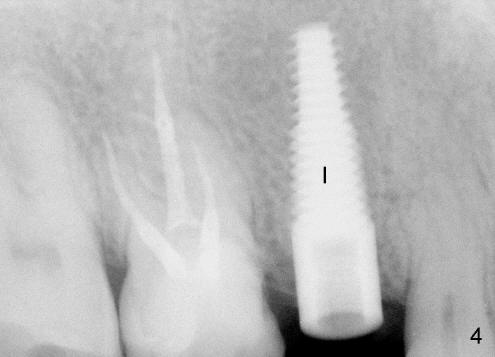

不过先做右上六根管治疗(图二:6),图二再次证实五号牙处骨头高度。